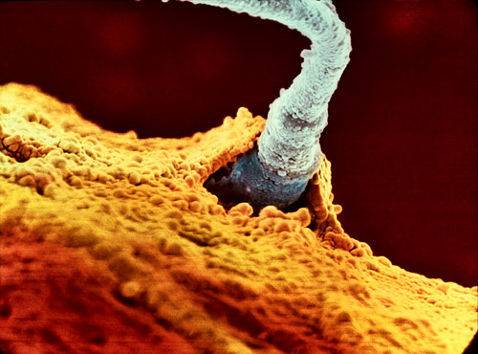

Најбрзиот сперматозоид ги победува останатите 200 милиони и навлегува во обвивката од јајцеклетката…